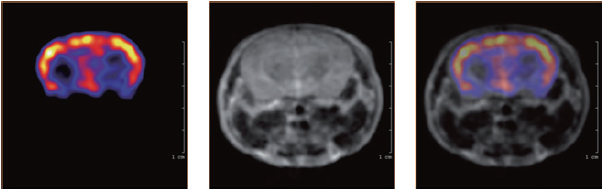

マウス脳内の18F-フルオロデオキシグルコース(FDG)集積

麻酔下マウス脳のフルオロデオキシグルコース(FDG)集積を示す3平面PET/MRI画像。

12MBq

18F-FDG 使用、[撮像時間] PET:60分、MRI:17.5分

Images courtesy of Karolinska Institute, Stockholm, Sweden